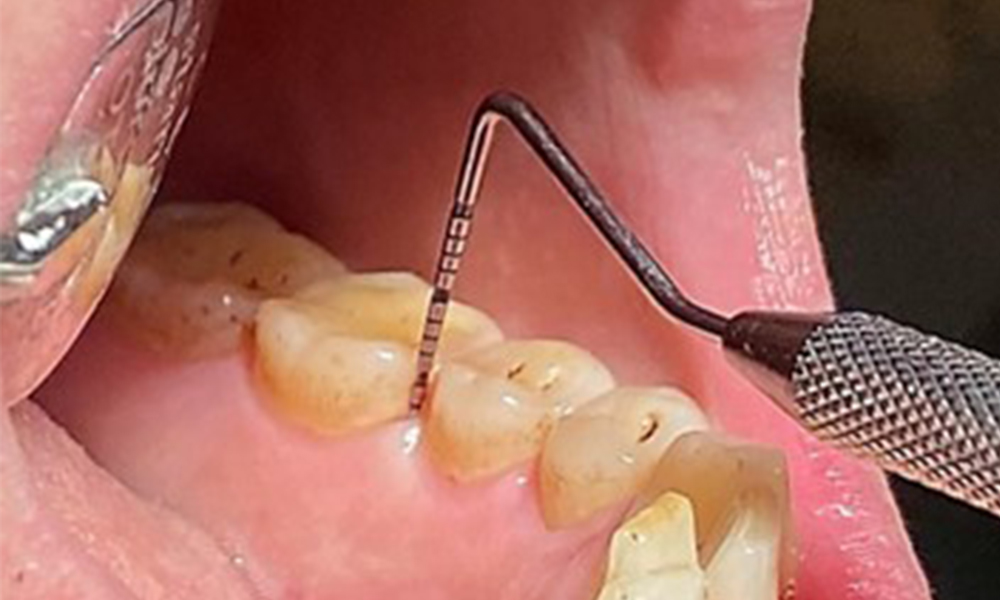

Due to the otherwise favourable general medical condition, the needs determined during the intraoral examination will be decisive for their treatment. It will be essential to periodically determine the probing depths. Gingival bleeding decreases in smokers, which is why the clinical diagnosis of periodontitis can only be made by probing (Fig. 7). Placing exclusive focus on the determination of bleeding indices may obscure existing periodontitis or gingivitis. (5)